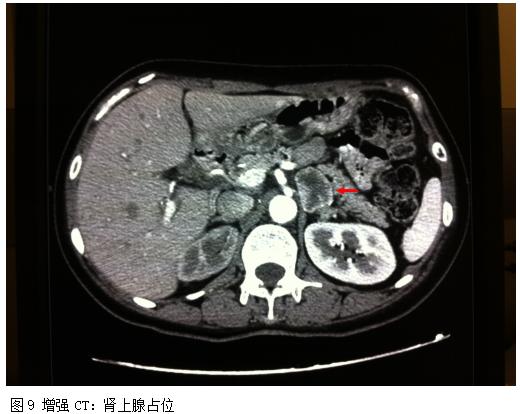

④入院第9天开始清晨出现头胀、心悸伴大汗,测心率、血压明显升高。此后每日清晨开始类似症状发作,持续1-4小时不等;心率在90-100次/分,血压高达190-220/100-120mmHg;下午血压在90-100/50-60mmHg。发作时复查心电图,再次出现多导联T波深倒为主的改变(图7、图8)。双侧肾上腺螺旋CT平扫+增强(图9):1.左肾上腺占位,性质待定,嗜铬细胞瘤?儿茶酚胺测定(平静时):去甲肾上腺素 61.53ng/ml,肾上腺素 0.90ng/ml,多巴胺 123.32ng/ml,均在正常范围内。血压200/100mmHg,伴头部胀痛感时:去甲肾上腺素 69.09ng/ml,肾上腺素 1.22ng/ml,多巴胺 122.14ng/ml,均在正常范围内。

结合患者的临床表现和影响学改变,肾上腺占位考虑诊断:嗜络细胞瘤可能。调整控制血压方案,以小剂量α和β阻滞剂起始:阿尔马尔5mg Qd、特拉唑嗪 1mg Qd 逐渐增至2mg(晨6:00服用),治疗1周以上,血压稳定,未再波动。行核素(I131-MIBG)检查:左肾上腺区团状放射性分布异常浓聚影,余未见异常。提示:左肾上腺区嗜铬细胞瘤。